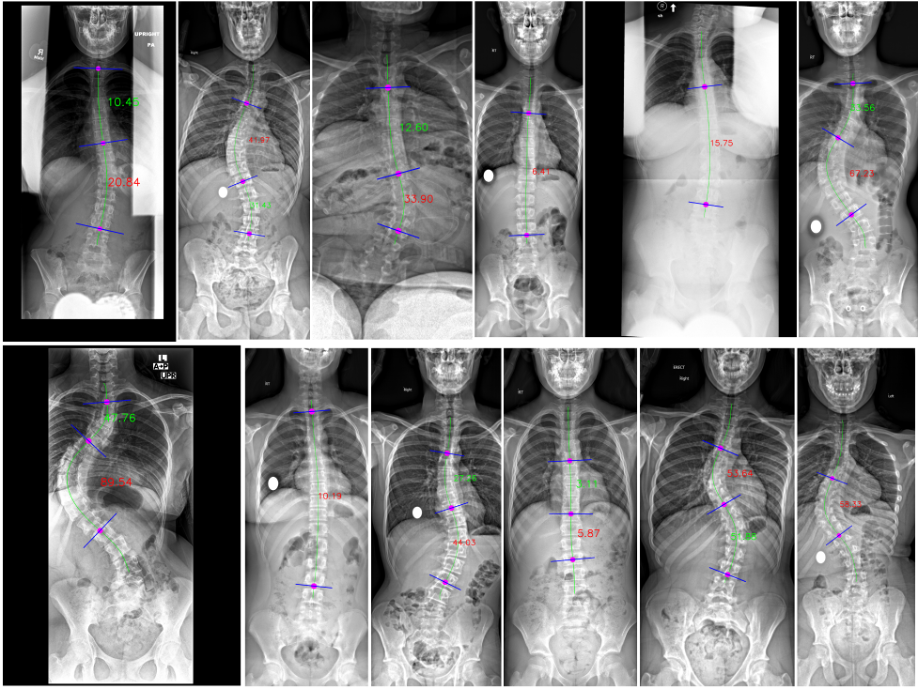

Figure 3: Measured examples of Cobb angles. They are automatically shown as the final outputs of our method, without any further manual sketching. The main Cobb angle is displayed in red lettering, while additional Cobb angles are displayed in green.

After measuring vertebral direction (90,90)superscript90superscript90(-90^{\circ},90^{\circ}). We then measured the Cobb angles between connected vertebrae. Figure 3 illustrates several examples of measured Cobb angles. Our approach depicted the Cobb angles and the vertebrae we referred to, and the main Cobb angle is the one we care most about and the one referred to decides the scoliosis severity [3], colored in red in Figure 3.

Figure 3 provides representative illustrations of the measurements derived from our algorithm. This figure elucidates the extracted spinal centerline, the quantified multi-point Cobb angles, and the orientation of the vertebrae, depicted via a concise blue line. As evidenced by the samples presented, our algorithm demonstrates consistent performance and robust stability across a diverse patient cohort, ranging in scoliosis severity and varying radiographic conditions.